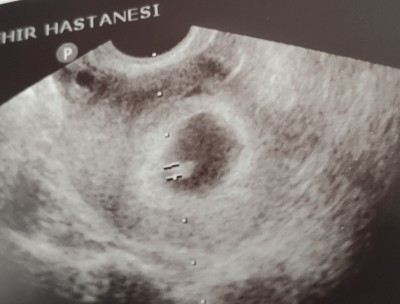

Merhaba geçen sormuştum yine soruyorum kesin bi cevap alamadım doktora gittim kalp atışı duyduk bebek iyi durumdaymis ama kese yamukmus ve düşük riski var dedi doktor 6 haftalık hiç kanama felanda olmadı yamuk kese olduğunu öğrenip doğum yapan var mi

Gebelik haftası 6